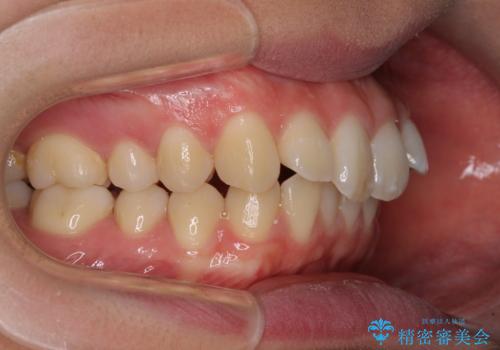

すきっ歯の改善 インビザライン矯正治療

- 上の前歯の隙間を気にして来院された患者様です。

インビザラインにより、上下の歯列を側方に拡大しつつ、前歯の隙間を閉じていくこととしました。

1日22時間の装着時間をしっかりと守ってくださったので、隙間がきれいに閉じ、口元の突出感も改善することができました。